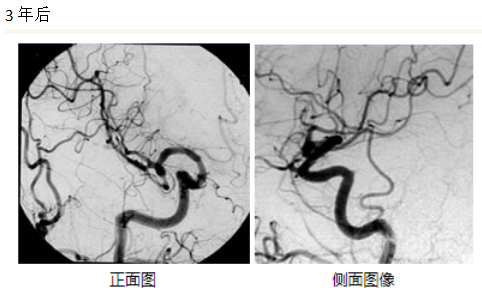

治疗结果根据病变的大小和部位有很大的差异,据报道,γ刀治疗的直径3cm以内的脑动静脉畸形的情况下,3年后的五年生存率约为60%-90%前后。下图为伽马刀治疗成功并完全阻塞的典型案例-伽玛刀脑血管造影术。